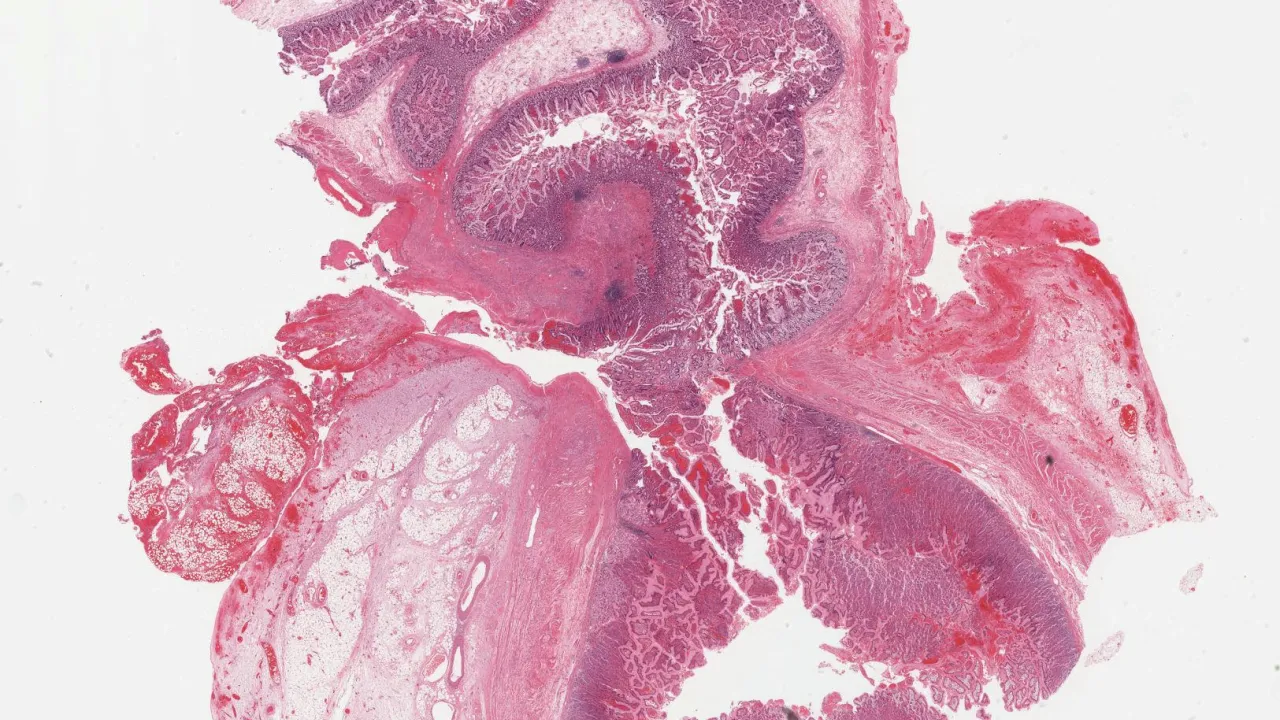

Abdomen, OEIS Complex

Bladder, OEIS Complex

Cloaca, OEIS Complex